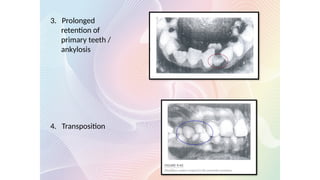

3. Prolonged

retention of

primary teeth /

ankylosis

4. Transposition